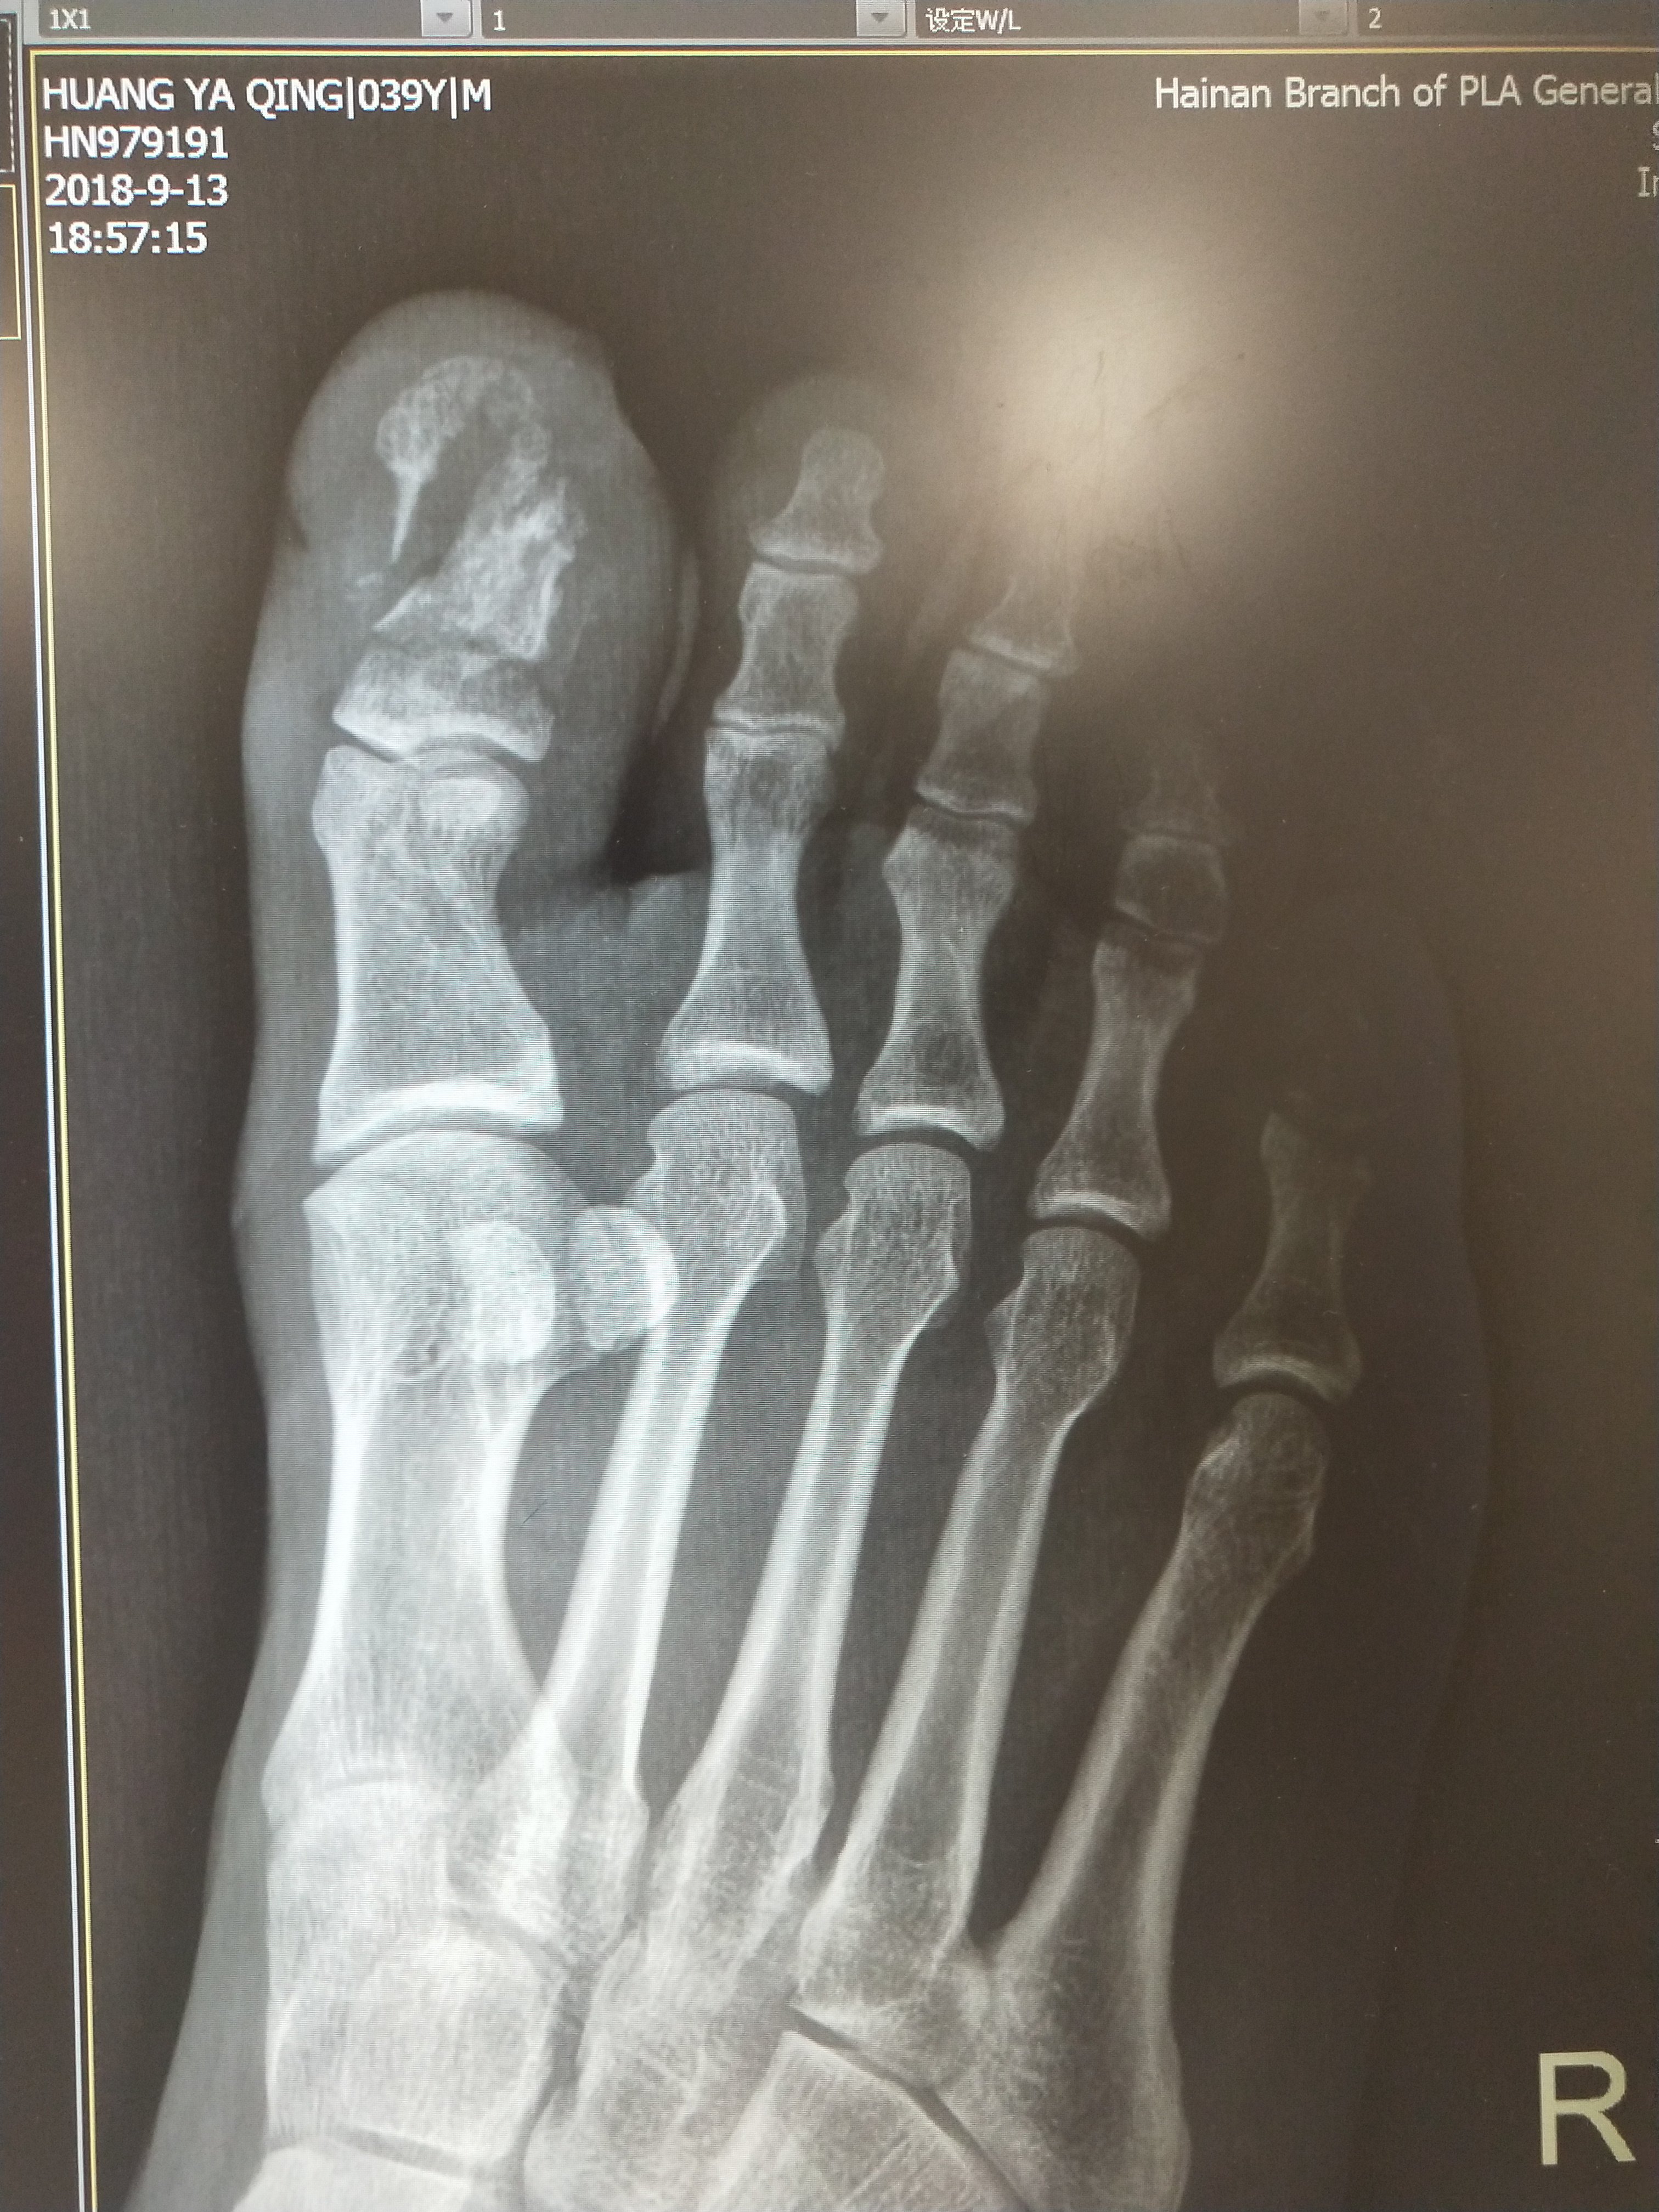

27/03/17 · 親指だけは末節骨と基節骨の二つからなっていますが、 他の4趾は同様の構造です。 基節骨よりもより近位の骨折は、 「中足骨骨折」と呼ばれています。 「中足骨骨折」 に関する記事はこちら → 「中足骨骨折」とは?治療期間や全治はどれくらい?

足趾 そくし の骨折 基節骨 きせつこつ の骨折 福岡の弁護士による後遺障害 等級認定サポート

末節骨骨折 発生頻度は指節骨骨折の中では最も多く,ま た開放骨折の頻度が高い.粗面部,骨幹部,基 部に分類され,骨片の安定性は爪甲による安定 性と腱停止部との関係に関連する. 粗面部骨折では爪甲が外固定がわりとなり,スクリュー固定 骨折部をネジのみで止める手軽な方法です。ピンニング同様、単純な骨折の場合にこの方法が選ばれます。 プレート固定 皮膚を切開して骨折した部分をプレートとスクリューを使って固定させる方法です。主に関節や関節近くの骨折に使われます。 髄内釘(ずいないてい)固�足指骨折(末節骨、中節骨、基節骨) 足の 指(末節骨、中節骨、基節骨) の骨折であればリハビリは行わないこともあります。骨がズレていない場合は固定は1~2週間ぐらいで、痛みに応じて踵歩行を行ってもらいます。 Jones骨折・第5中足骨疲労骨折 Jones骨折とは? 第5中足骨疲労骨折は

親指の末節骨は粉砕骨折となる事があります。 骨折するとどうなるの? 治療を受けるべき目安 足の指が反対側と比べると曲がっている → 骨が曲がって折れている (完全骨折)または脱臼をしている可能性 があります。整復(引っ張って元に戻す)と固定が固定をして2~3週間は安静にしてもらいある程度骨が安定するまで固定をします。 固定中も指を動かすことを許可し電気療法や手技療法による刺激を加えて骨折の回復を早めていきます。 3週後 長軸 3週後 長軸 患側と健側しかし爪は添え木の役目を果たす場合もあるので、末節骨の単純骨折の場合、患者様のqolを考えた最小限の固定で治療が可能です。 当院の治療法 当院では、超音波画像にて状態を確認し、その後必要に応じて提携病院にて精検をお願いしております。 この場合、いかに日常生活に支障がない